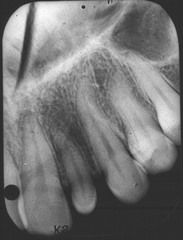

-obstruction in the gland hard nodule in soft tissue at a salivary gland -calcification of material -can be seen radiographically